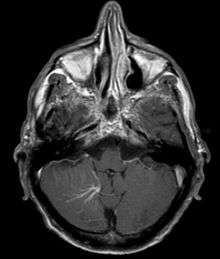

Developmental venous anomaly in the cerebellum seen on axial contrast-enhanced T1 weighted MRI.

A developmental venous anomaly (DVA, formerly known as venous angioma) is a congenital variant of the cerebral venous drainage. On imaging it is seen as a number of small deep parenchymal veins converging toward a larger collecting vein.